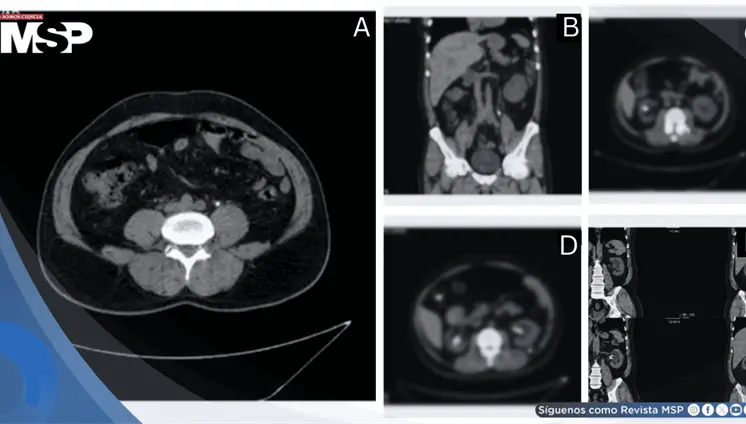

La paciente presentó cambios en el hábito intestinal y sangrado rectal con imágenes compatibles con lesiones estenosantes, inicialmente sospechosas de neoplasia sincrónica.